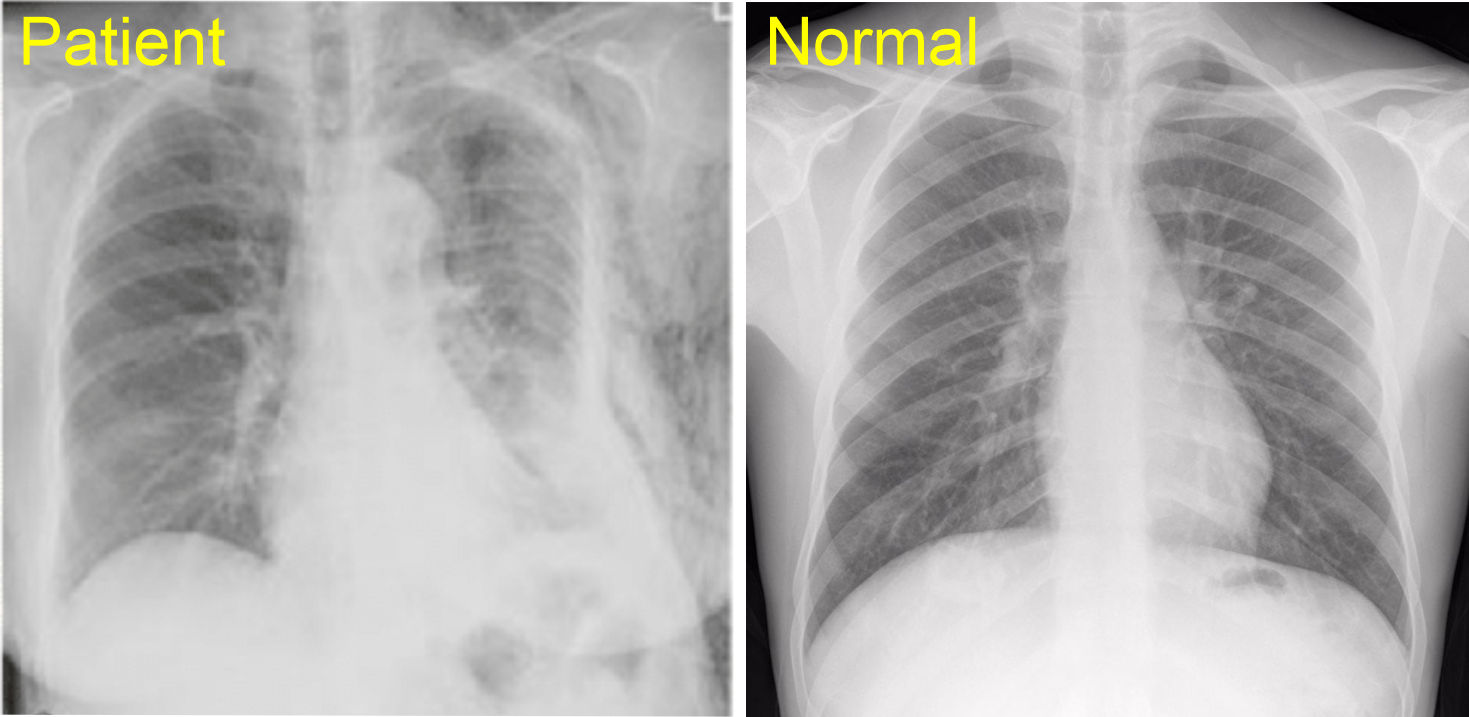

A patient was in a side car impact where the drivers side door collapsed inward impacting the anterolateral aspect of the patients left torso. The patient indicates they have extreme pain when moving their left arm and shortness of breath. The pain is significantly stronger than during quiet breathing. When moving the arm back and forth you hear a 'clicking' - Click here for sound - A chest film is ordered and shows